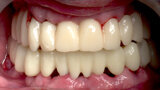

The fully digital Pro Arch protocol